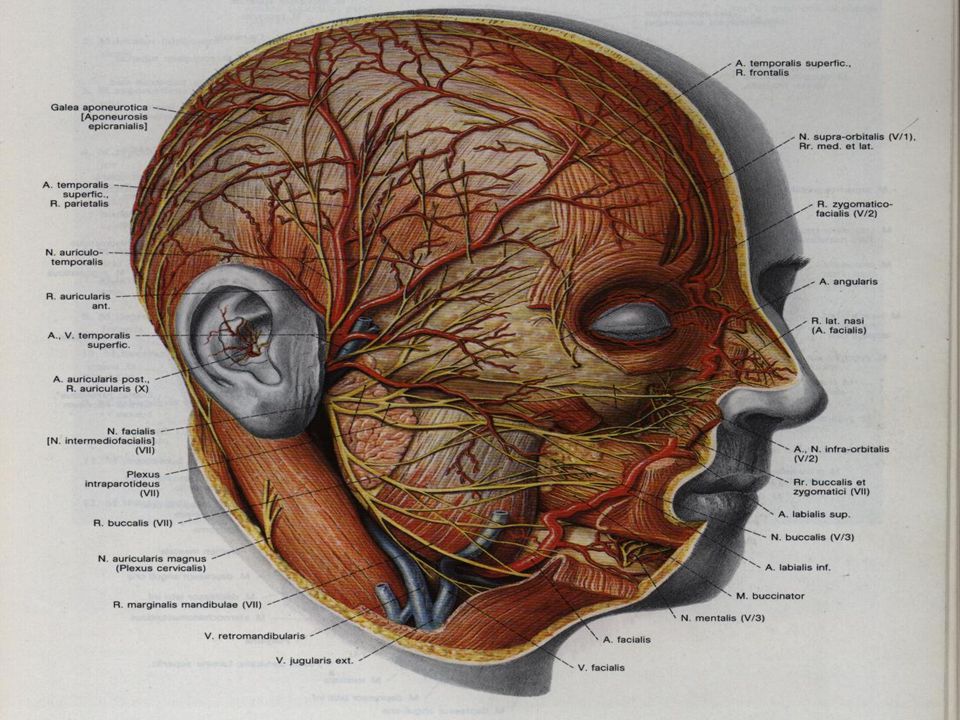

Анатомия и особенности фиссуры петротимпаника